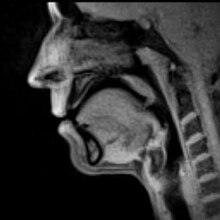

Real-time MRI of speech production at a temporal resolution of 33 m

Im weiteren Sinne untersucht die forensische Linguistik auch Themen wie die Verständlichkeit von Gesetzestexten und die Sprache vor Gericht. Die forensische Sprechererkennung und Tonträgerauswertung wird nicht isoliert in Deutschland angewendet, sondern ist Teil eines internationalen Netzwerkes von Aktivitäten. Wichtige Berufs- und Forschungsorganisationen sind die „International Association for Forensic Phonetics and Acoustics„, „International Association of Forensic Linguists„ und ENFSI (European Network of Forensic Science). In diesem wissenschaftlichen Verbund werden u.a. auch Richtlinien über ethisch korrektes und wissenschaftlich hochwertiges Verhalten als (forensischer) Sachverständiger für dieses Fachgebiet erarbeitet.